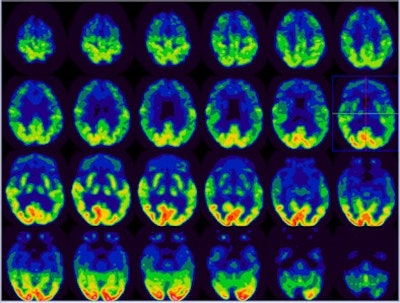

![]() |

| In this image of diffuse cortical hypometabolism, there is moderately reduced FDG activity in the entire cerebral cortex relative to the basal ganglia. The pattern of diffuse hypometabolism is not suggestive of specific dementia syndrome. The finding is more compatible with diffuse metabolic insult or medication effect. |